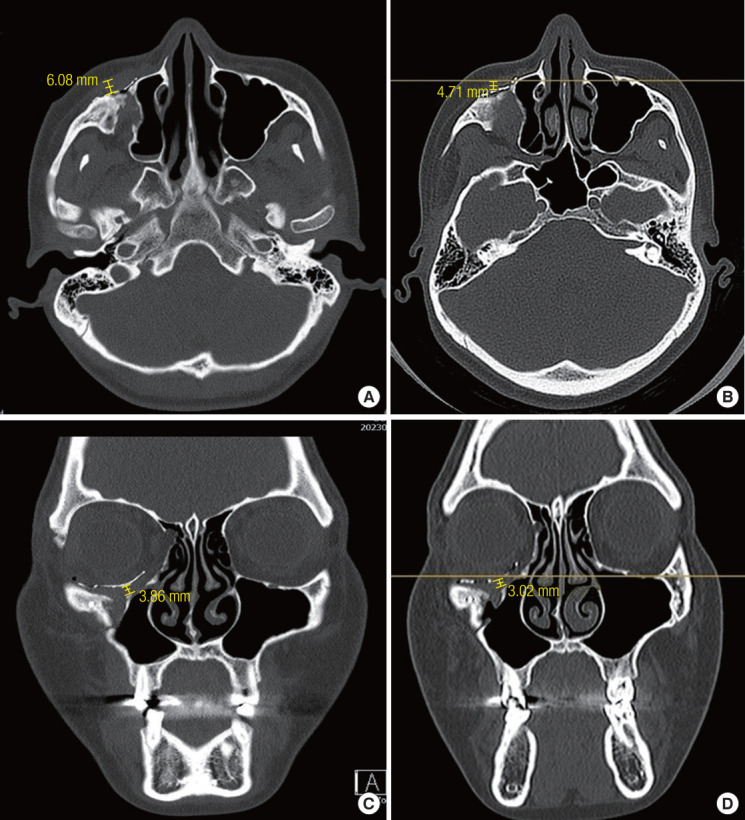

This paper presents a novel approach to the correction of zygomatic malposition and secondary reconstruction orbital floor fractures, highlighting the use of hydrated acellular dermal matrix (ADM), specifically CGDerm One-Step, in a case where traditional solid implants failed to maintain structural integrity and volume. A 27-year-old woman with persistent facial deformities following a traumatic incident underwent a transformative procedure that utilized ADM for volume correction and structural support, addressing significant challenges such as enophthalmos and facial contour depression. This approach was necessitated by the descent of the entire orbital floor and a previously placed implant (Medpor), leading to unsatisfactory volume correction. By integrating ADM with titanium-reinforced fan plates (Synpor), the surgery successfully restored the patient's facial symmetry and addressed her functional concerns, including diplopia and limited eye movement. Postoperative evaluations demonstrated the long-term effectiveness of this method, with significant improvements in facial contour and eye symmetry. Our findings suggest that ADM, particularly in its hydrated form, offers a reliable alternative to traditional bone grafts and implants for correcting complex craniofacial deformities, providing both aesthetic and functional benefits. This case underscores the importance of adaptable, tissue-mimicking materials in facial reconstructive surgery, offering insights into their potential for broader application in post-traumatic facial corrections.